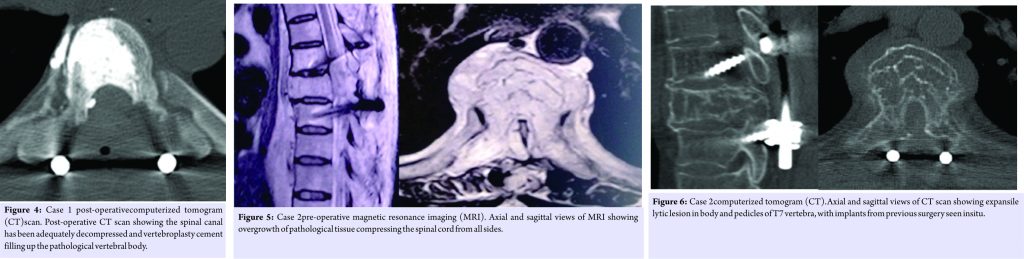

Standard midline posterior approach was used to expose T4 to T8 laminae. T5-6 laminectomy was performed. Bony tumor mass was found arising from left T6 lamina and pedicle; which was carefully drilled out with high-speed burr. Cord decompressed from T5 to T7. Pedicle screw fixation was done from T4 to T8 and vertebroplasty into T6 body (Fig. 3 and 4). Histology of tumor showed benign capillary hemangioma. In the post-operative period, spasticity improved rapidly. The patient was walking with the support of walker from 4th post-operative day. Postoperatively, the patient received low-dose radiotherapy. Neurological recovery was almost complete over a period of 6 months, except for mild numbness over both lower limbs, modified JOA score7 (using lower extremity score only).

A male patient aged 71 years presented with recurrence of hemangioma with cord compression was selected. He had a history of hemangioma with cord compression 13 years back, which was then managed with embolization, followed by decompression and fixation andhistologically proved to be benign capillary hemangioma. The patient had gradually improved neurologically to normal activities. He was asymptomatic till 7 months back when he started having difficulty in walking, which was progressive. Bowel and bladder control was preserved. Nurick Grade 3 and modified JOA score (using lower extremity score only) was 3. On physical examination, the patient had myelopathic gait. Higher motor function and upper limb examination were within the normal limits. Both lower limbs were spastic. Motor power Grade was 5/5 in both lower limbs. Hypoesthesiawas below T10. Both lower limb deep tendon reflexes were exaggerated; however, Babinski’s sign was negative. Radiographic examination showed coarse vertical striations in T7 vertebral body with pedicle screw fixation T6 to T8. MRI and CT scan examination showed bony growth involving T7 body and both pedicles, encasing and compressing the spinal cord (Fig. 5, 6, 7). Embolization was carried out, followed by surgical decompression. With the patient in prone position, midline posterior approach was used to expose T4 to T10 laminae. Pedicles screws and rods of previous surgery were removed. One pedicle screw was broken and had to be left behind. Spinal cord decompressed from T6 to T8 posteriorly and transpedicular decompression at T7. Pedicle screw fixation wasdone from T4 to T10 and vertebroplasty at T7 (Fig. 8, 9). Histological examination of tumor showed benign capillary hemangioma. Postoperatively, the patient received radiotherapy. Neurological recovery was almost complete (modified JOA score 6) at 6-month follow-up (Fig. 10).